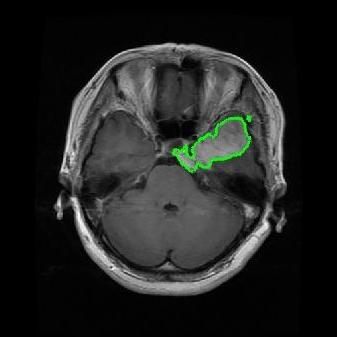

From the above discussions, we have discovered the significant potential of applying Retinex theory to image segmentation and explored its fundamental differences from traditional models. Traditional image segmentation models typically focus on the impact of intensity information on the segmentation results. Therefore, when faced with complex segmentation scenarios, the segmentation results are often affected by lighting, artifacts, and unclear boundaries in the image. As shown in Fig. 1, we present the results of the classical local model LIF [ZHANG20101199] for segmenting brain tumor images along with surrounding tissue edema. The irregular ring-like enhancement caused by the edematous tissue leads to irregular boundaries and low contrast in the images. Consequently, the LIF model can only identify the central necrotic and liquefied regions of the tumor, failing to detect the boundaries and becoming trapped in local minima. In this paper, we draw inspiration from the Retinex theory, which is widely applied in the field of image enhancement. According to Retinex theory, the reflectance component characterizes the intrinsic structural properties of the observed image and preserves texture information independent of illumination variations. By integrating this reflectance component into the level set framework, our model achieves robust segmentation of medical images even under severe intensity inhomogeneity. In addition, a linearized Structural-Prior is proposed to restore intensity consistency and capture local geometric features, thereby improving boundary localization in complex or blurred regions. Furthermore, a relaxed binary level set representation is employed to enhance robustness against noise and to enable accurate tracking of complex contours. Based on these innovations, we propose a novel variational reflectance-based level set model (RefLSM) that simultaneously corrects bias fields and performs segmentation. Experimental results demonstrate that RefLSM significantly outperforms conventional level set methods in both segmentation accuracy and robustness. We present the results of our model segmenting the two brain tumor images mentioned above in Fig. 2.

To address the challenge of segmenting images with severe intensity inhomogeneity, we propose a linearized structural prior that directly operates on the reflectance component . Reflectance-based structural information is more robust to illumination variations and bias field distortions, helping preserve weak edges and subtle anatomical boundaries. As shown in Fig. 2, our method can accurately delineate tumor boundaries and surrounding edema even under severe inhomogeneity, where traditional intensity-based models often fail. The proposed prior aligns smoothed reflectance gradients with data-driven directions, enhancing inter-region contrast, preserving weak edges, and stabilizing the evolution of . Formally, we define the linear structure operator as the gradient field of the smoothed reflectance: